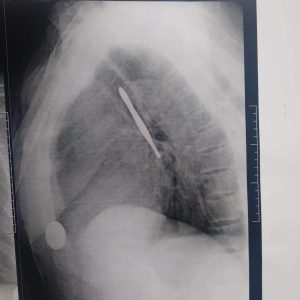

نجح فريق جراحي بقسم جراحة القلب والصدر بمستشفى بنها الجامعي بمحافظة القليوبية، في استخراج “ملقاط شعر”، من القصبة الهوائية لمريض يعاني من شق حنجري قديم، وأثناء قيامه بتنظيف فتحة الشق الحنجري بطريقة غير طبية وغير صحيحة باستخدام الملقاط ملفوف بمناديل ورقية، سقط منه وابتلعه ودخل لفتحة القصبة الهوائية.

وأوضح مستشفى بنها الجامعي، فى بيان له، أنه جرى الآن استخراج “ملقاط شعر” من القصبة الهوائية لمريض يعاني من شق حنجري قديم، وبينما يقوم بتنظيف فتحة الشق الحنجري بطريقة غير طبية وغير صحيحة باستخدام ملقاط ملفوف بمناديل ورقية اتشفط منه الملقاط ودخل لفتحة القصبة الهوائية.

وتابع المستشفى، أنه حضر المريض للقسم في حالة اختناق، وتم دخوله العمليات فورا، حيث نجح الدكتور باسم مفرح الأستاذ المساعد بالقسم، وبمعاونة الدكتور أحمد الخضري مدرس مساعد التخدير، من استخراج “الملقاط”، وخرج المريض بسلامة الله من العمليات ويخضع لاستكمال علاجه بالقسم لحين تماثله الكامل للشفاء.